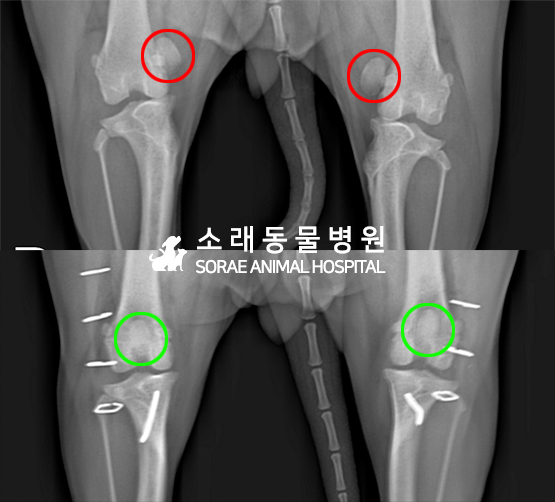

수술전과 수술후에 촬영한 조이의 슬개골

방사선 사진입니다. 나란히 놓고 비교해보니

슬개골의 위치에 확연한 차이가 있는 것을

확인해 볼 수 있는데요. 내측으로 탈구되어 있던

슬개골이 원래 제자리인 활차구에 예쁘게

자리 잡고 있는 모습을 확인할 수 있었습니다.